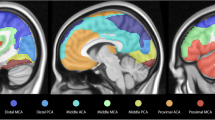

The acquisition of bh-fMRI was feasible in 9/10 cases. One participant with left temporal lobe epilepsy was unable to comply with the breathing maneuvers and was excluded from further analysis after inspection of the signal response curve demonstrated poor data quality. We observed no adverse events, and none of the participants reported any discomfort related to intermittent hypercapnia. All participants, except for participant 6, did not have a seizure for 24 h before bh-fMRI acquisition. Exemplary results of bh-fMRI are shown as normalized cerebrovascular reactivity (CVR) maps in Fig. 1. Fig. 1a demonstrates a focal absence of relative signal increase after breath-hold maneuvers, which corresponds to an impaired CVR (red) in the left temporal region (arrow). This is consistent with the irritative zone and seizure-onset zone of participant 8. Fig. 1b demonstrates impaired CVR primarily in the right temporal region (red, straight arrow) and secondarily in the right temporo-occipital region (light green, curved arrow) which is likewise consistent with the irritative zone and seizure onset zone of participant 6. We found the cerebellar reference signal to be reproducible across the seven breath-hold periods (Fig. 2a), with an average Pearson’s correlation coefficient of 0.814. Likewise, quantitative BOLD measurements were consistent across volumes-of-interest and highlighted regions of impaired stimulus-related signal increase, e.g., in the left superior temporal regions of participant 1 (Fig. 2b). The electroclinical features, epileptogenic zone localization hypothesis, and results of bh-fMRI for all cases are summarized in Table 1.

Exemplary normalized cerebrovascular reactivity (CVR) maps, shown as twelve representative axial slices for each study participant. a Participant 8. b Participant 6. Images are color-coded to represent the relative change in BOLD fMRI signal after breath-hold maneuvers, with impaired cerebrovascular reactivity shown in red. The color scale representing cerebrovascular reactivity is shown in the plot legend. Regions of interest are labelled (arrows)